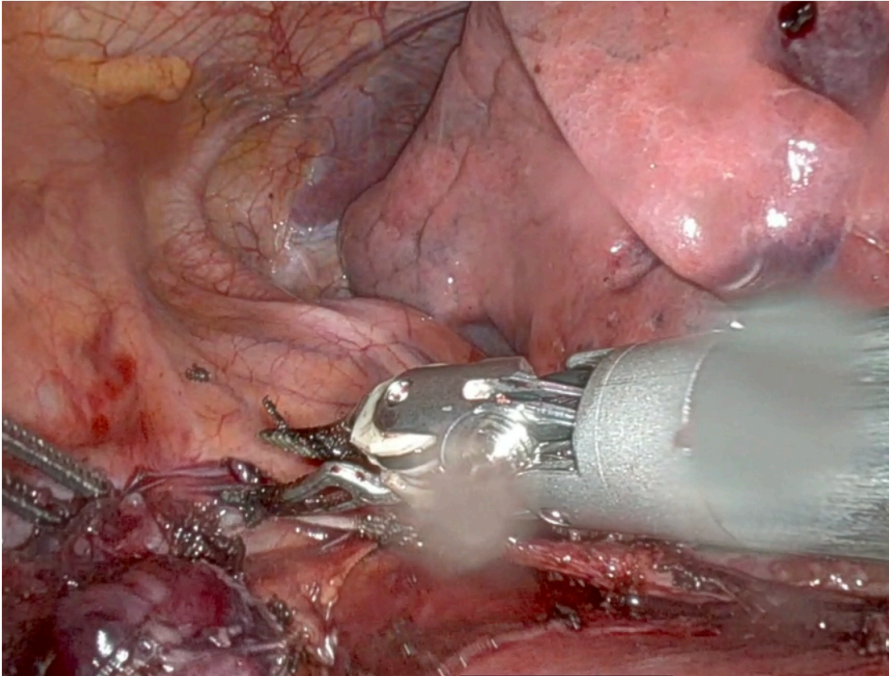

The tumor was located on the left side of the mediastinum, tenaciously adherent to the phrenic bundle. However, there was no direct infiltration of the nerve, and the surgeons were able to carefully dissect and preserve the nerve along its length across the left mediastinal side.

After dissecting the fat tissue from the right phrenic nerve, the surgeons proceeded to dissect the mediastinal tissue from the cava vein until they encountered the anonymous vein. Once the anonymous vein was identified, the surgeons dissected the upper horns, stripping the fat tissue from the lower part of the neck. The thymic vein was safely divided with Syncrosyl without the need for clips or Hem-o-lok. The specimen was extracted safely

When performing an extended thymectomy, it is mandatory to dissect all the anterior mediastinal fat from phrenic to phrenic, as oncological criteria suggest. Sometimes the lesion can present a close extension to the phrenic nerve path. Preserving the nerve is fundamental to avoid any postoperative immediate and long-term complications (e.g., paralysis, diaphragmatic relaxation, respiratory failure).

2C: Safe Phrenic Dissection